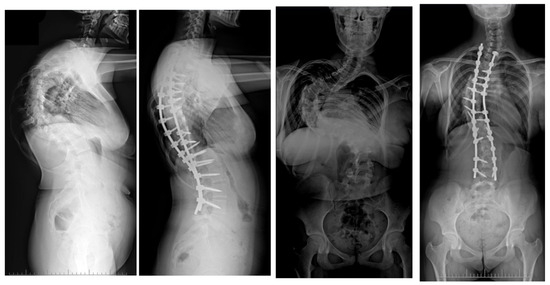

10. Rib Resection/Thoracoplasty

11. Author’s Preferred Technique